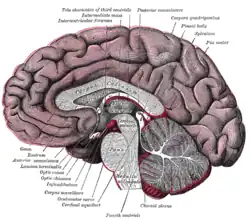

Cross-section of the brain showing the right cerebral hemisphere. The septum pellucidum is seen as the sheet joining the corpus callosum to the fornix. | |

The septum pellucidum (Latin for "translucent wall") is a thin, triangular, vertical double membrane separating the anterior horns of the left and right lateral ventricles of the brain. It runs as a sheet from the corpus callosum down to the fornix.

The septum pellucidum is located in the septal area in the midline of the brain between the two cerebral hemispheres. The septal area is also the location of the septal nuclei. It is attached to the lower part of the corpus callosum, the large collection of nerve fibers that connect the two cerebral hemispheres. It is attached to the front forward part of the fornix. The lateral ventricles sit on either side of the septum.